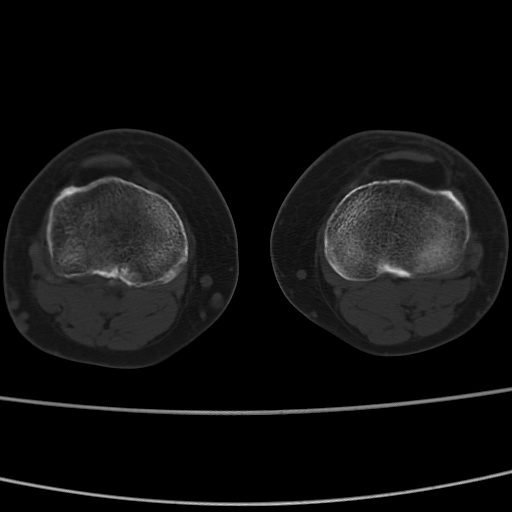

女性,50岁。【请提供患者临床症状体征】

右膝关节退行性改变,关节游离鼠。

右膝关节退行性改变,滑膜黏液囊钙/骨化并游离。